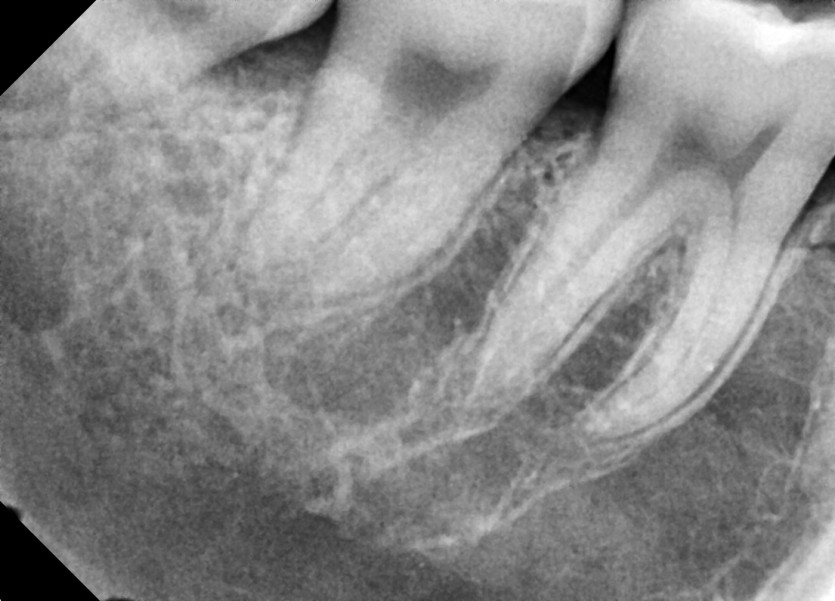

#18,48 사랑니 발치

구강외과 전문의가 당일발치 했습니다.